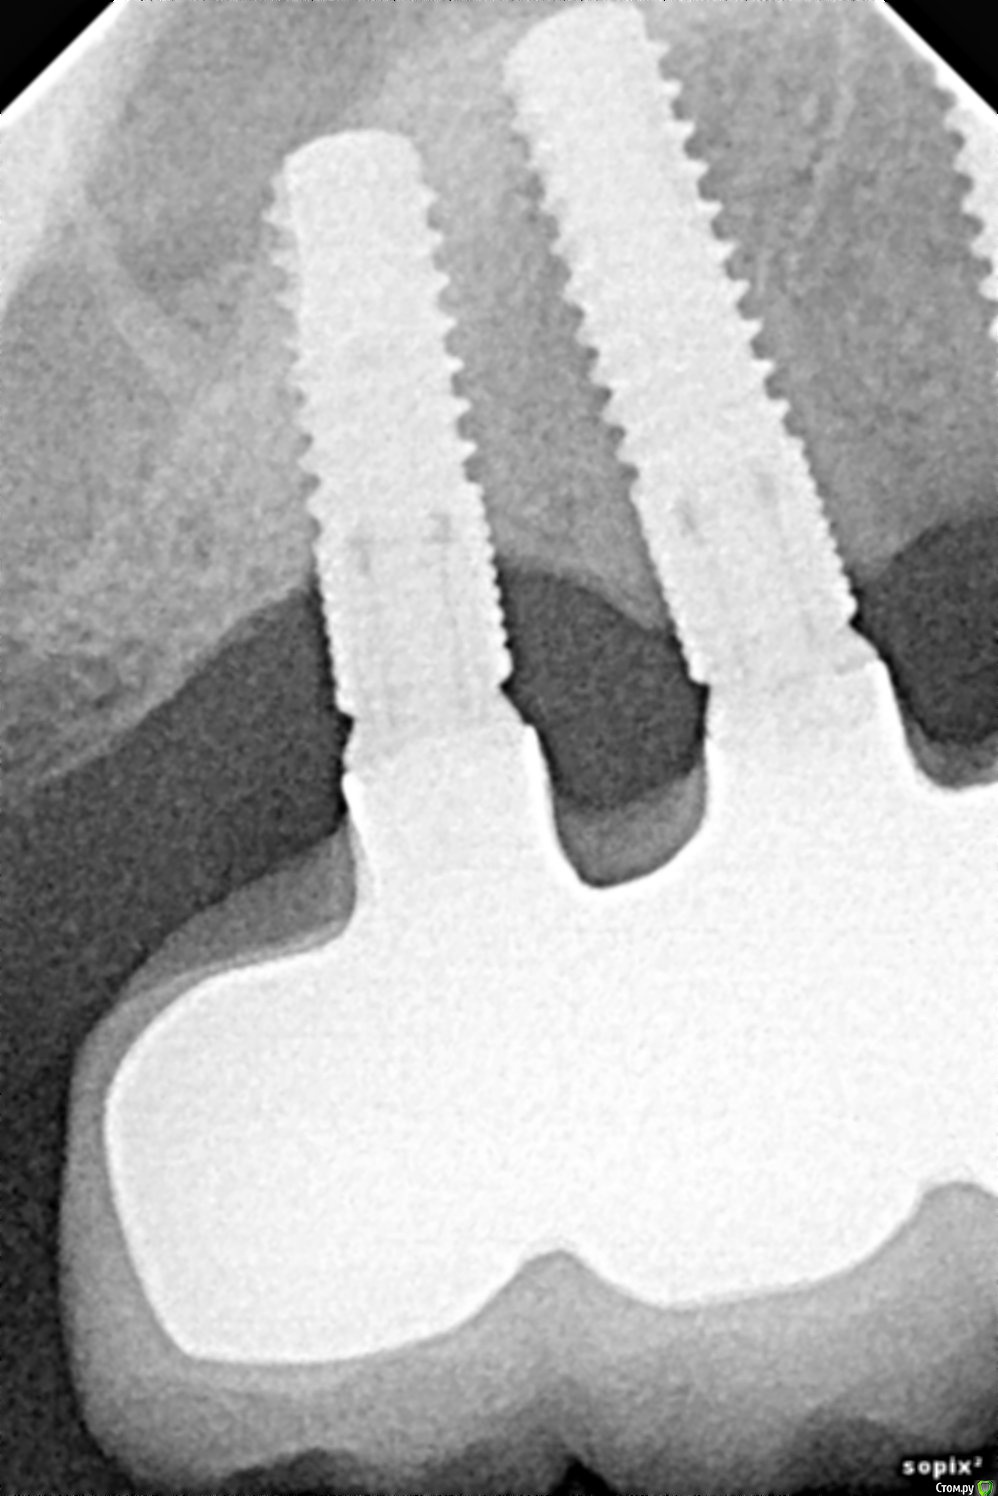

Имплантаты Конмет, установлены и запротезированы в 2010-2011 г. На данный момент пациента беспокоит только наличие сколов керамики. Учитывая атрофию костной ткани ( особенно у 1.7), какую хир. подготовку можно провести? Стоит ли объединять данные имплантаты с другими ( установленными в 2017 г. во фронтальном отделе)? И самое главное: какие возможны последствия (появление воспаления или подвижности), через какое время и как они могут сказаться?

post-46579-0-50136800-1499673819_thumb.jpg